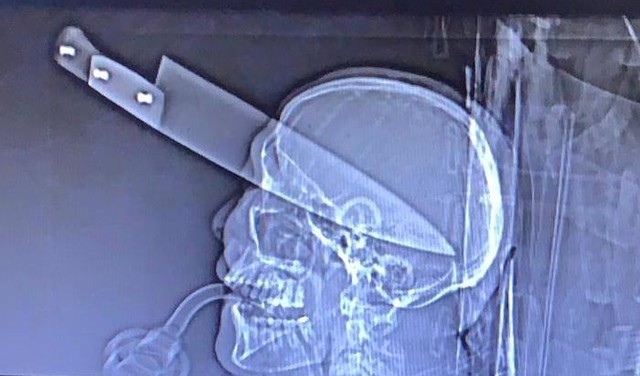

Homem sobrevive a facada no olho e é atendido com a arma ainda no crânio

No domingo (23), um homem foi encontrado dentro do carro com uma faca cravada no olho, em Dourados, região sul de Mato Grosso do Sul. A vítima foi identificada como Moisés de Oliveira, de 38 anos, ele segue internado em estado grave.

De acordo com o médico do Serviço de Atendimento Médico de Urgência (Samu), Renato Vidigal, o caso é grave:

“É raro de se ver na medicina. A faca transfixou todo o crânio do paciente e atingiu o cérebro, pegou massa cerebral.” Segundo o médico, antes do Samu chegar, alguém tentou retirar a faca do crânio da vítima, o que pode ter agravado o estado de saúde dele.